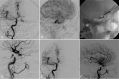

Fig. 2.

A, Left CCA angiogram lateral projection shows dural CCF fed by meningohypophyseal artery, accessory middle meningeal artery, and artery of foramen rotundum. The venous drainages are abnormally dilated left SOV and superior petrosal sinus. The IPS appeared occluded. B, Superselective venogram of the left SOV lateral view demonstrates multiple catheter support system with a 6F angled Envoy guiding catheter in the proximal left facial vein, a 4F Tracker 38 catheter in the left angular vein, and an Echelon 10 microcatheter. C, Postembolization with coils and Onyx angiogram of the left CCA shows complete occlusion of the fistula with no residual filling.

Fig. 3.

A, Right CCA injection lateral projection demonstrates dural CCF, with feeders from meningohypophyseal trunk with early venous drainage into the right SOV. The IPS is not visualized. No contribution of ECA was appreciated. B, Transexternal jugular-facial venous access is seen on the lateral projection with a 5F Glidecath XP in the right facial vein and a Prowler 14 microcatheter in the cavernous sinus/SOV junction, and deployed coils. C, Postprocedure right CCA angiogram lateral projection shows complete occlusion of the fistula with deployed coil mass and Onyx cast. A small piece of dislodged Onyx cast is also shown in the distal segment of right SOV.